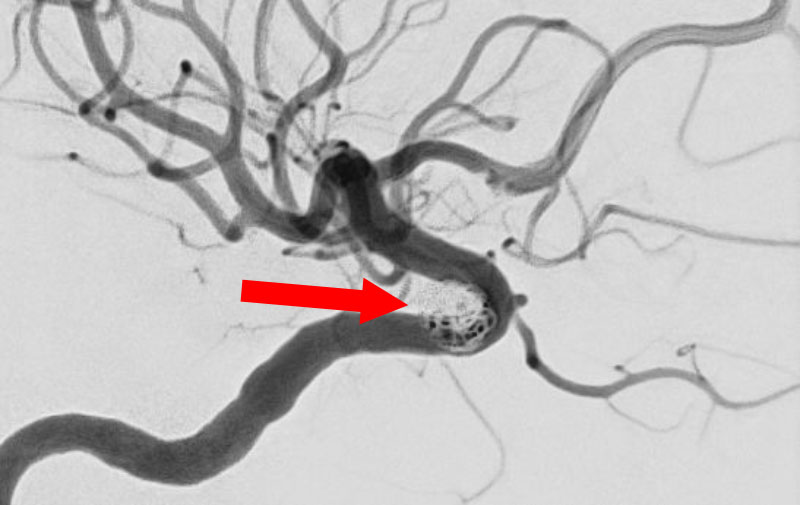

No.1596 手術前

'25年11月

左内頚動脈脳動脈瘤

60代

大阪府の病院